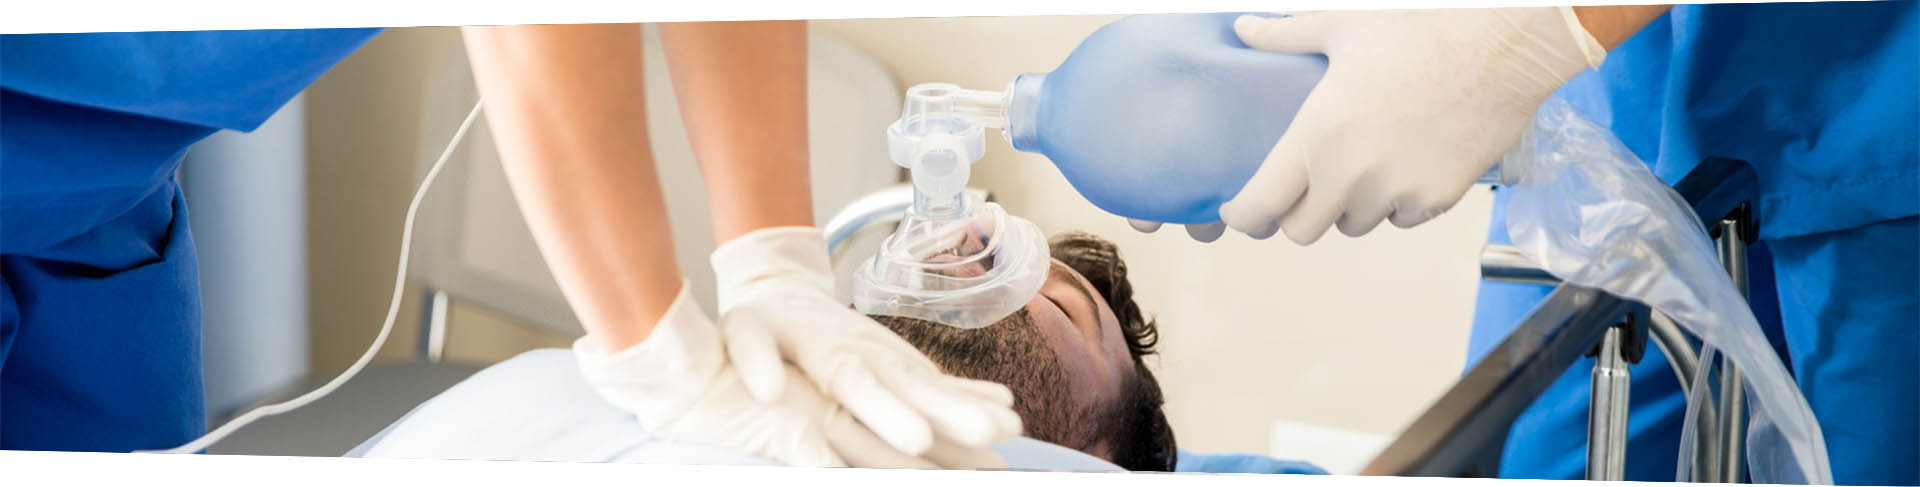

“生命高于一切,安全永远在前”,这是赏金船长官网新材医疗材料研发的出发点和使命。赏金船长官网新材为客户提供安全、高性能的TPU材料,具有良好的生物稳定性、适应性、高强度、加工通用性和绿色环保的循环处理能力,可用于制作输液软管、防护服薄膜、手套、药物容器、仿生假体等产品。

Mirathane®TPU与合作伙伴积极创造先进医疗技术的改革创新,由此诞生的专属医疗材料享誉全球临床。